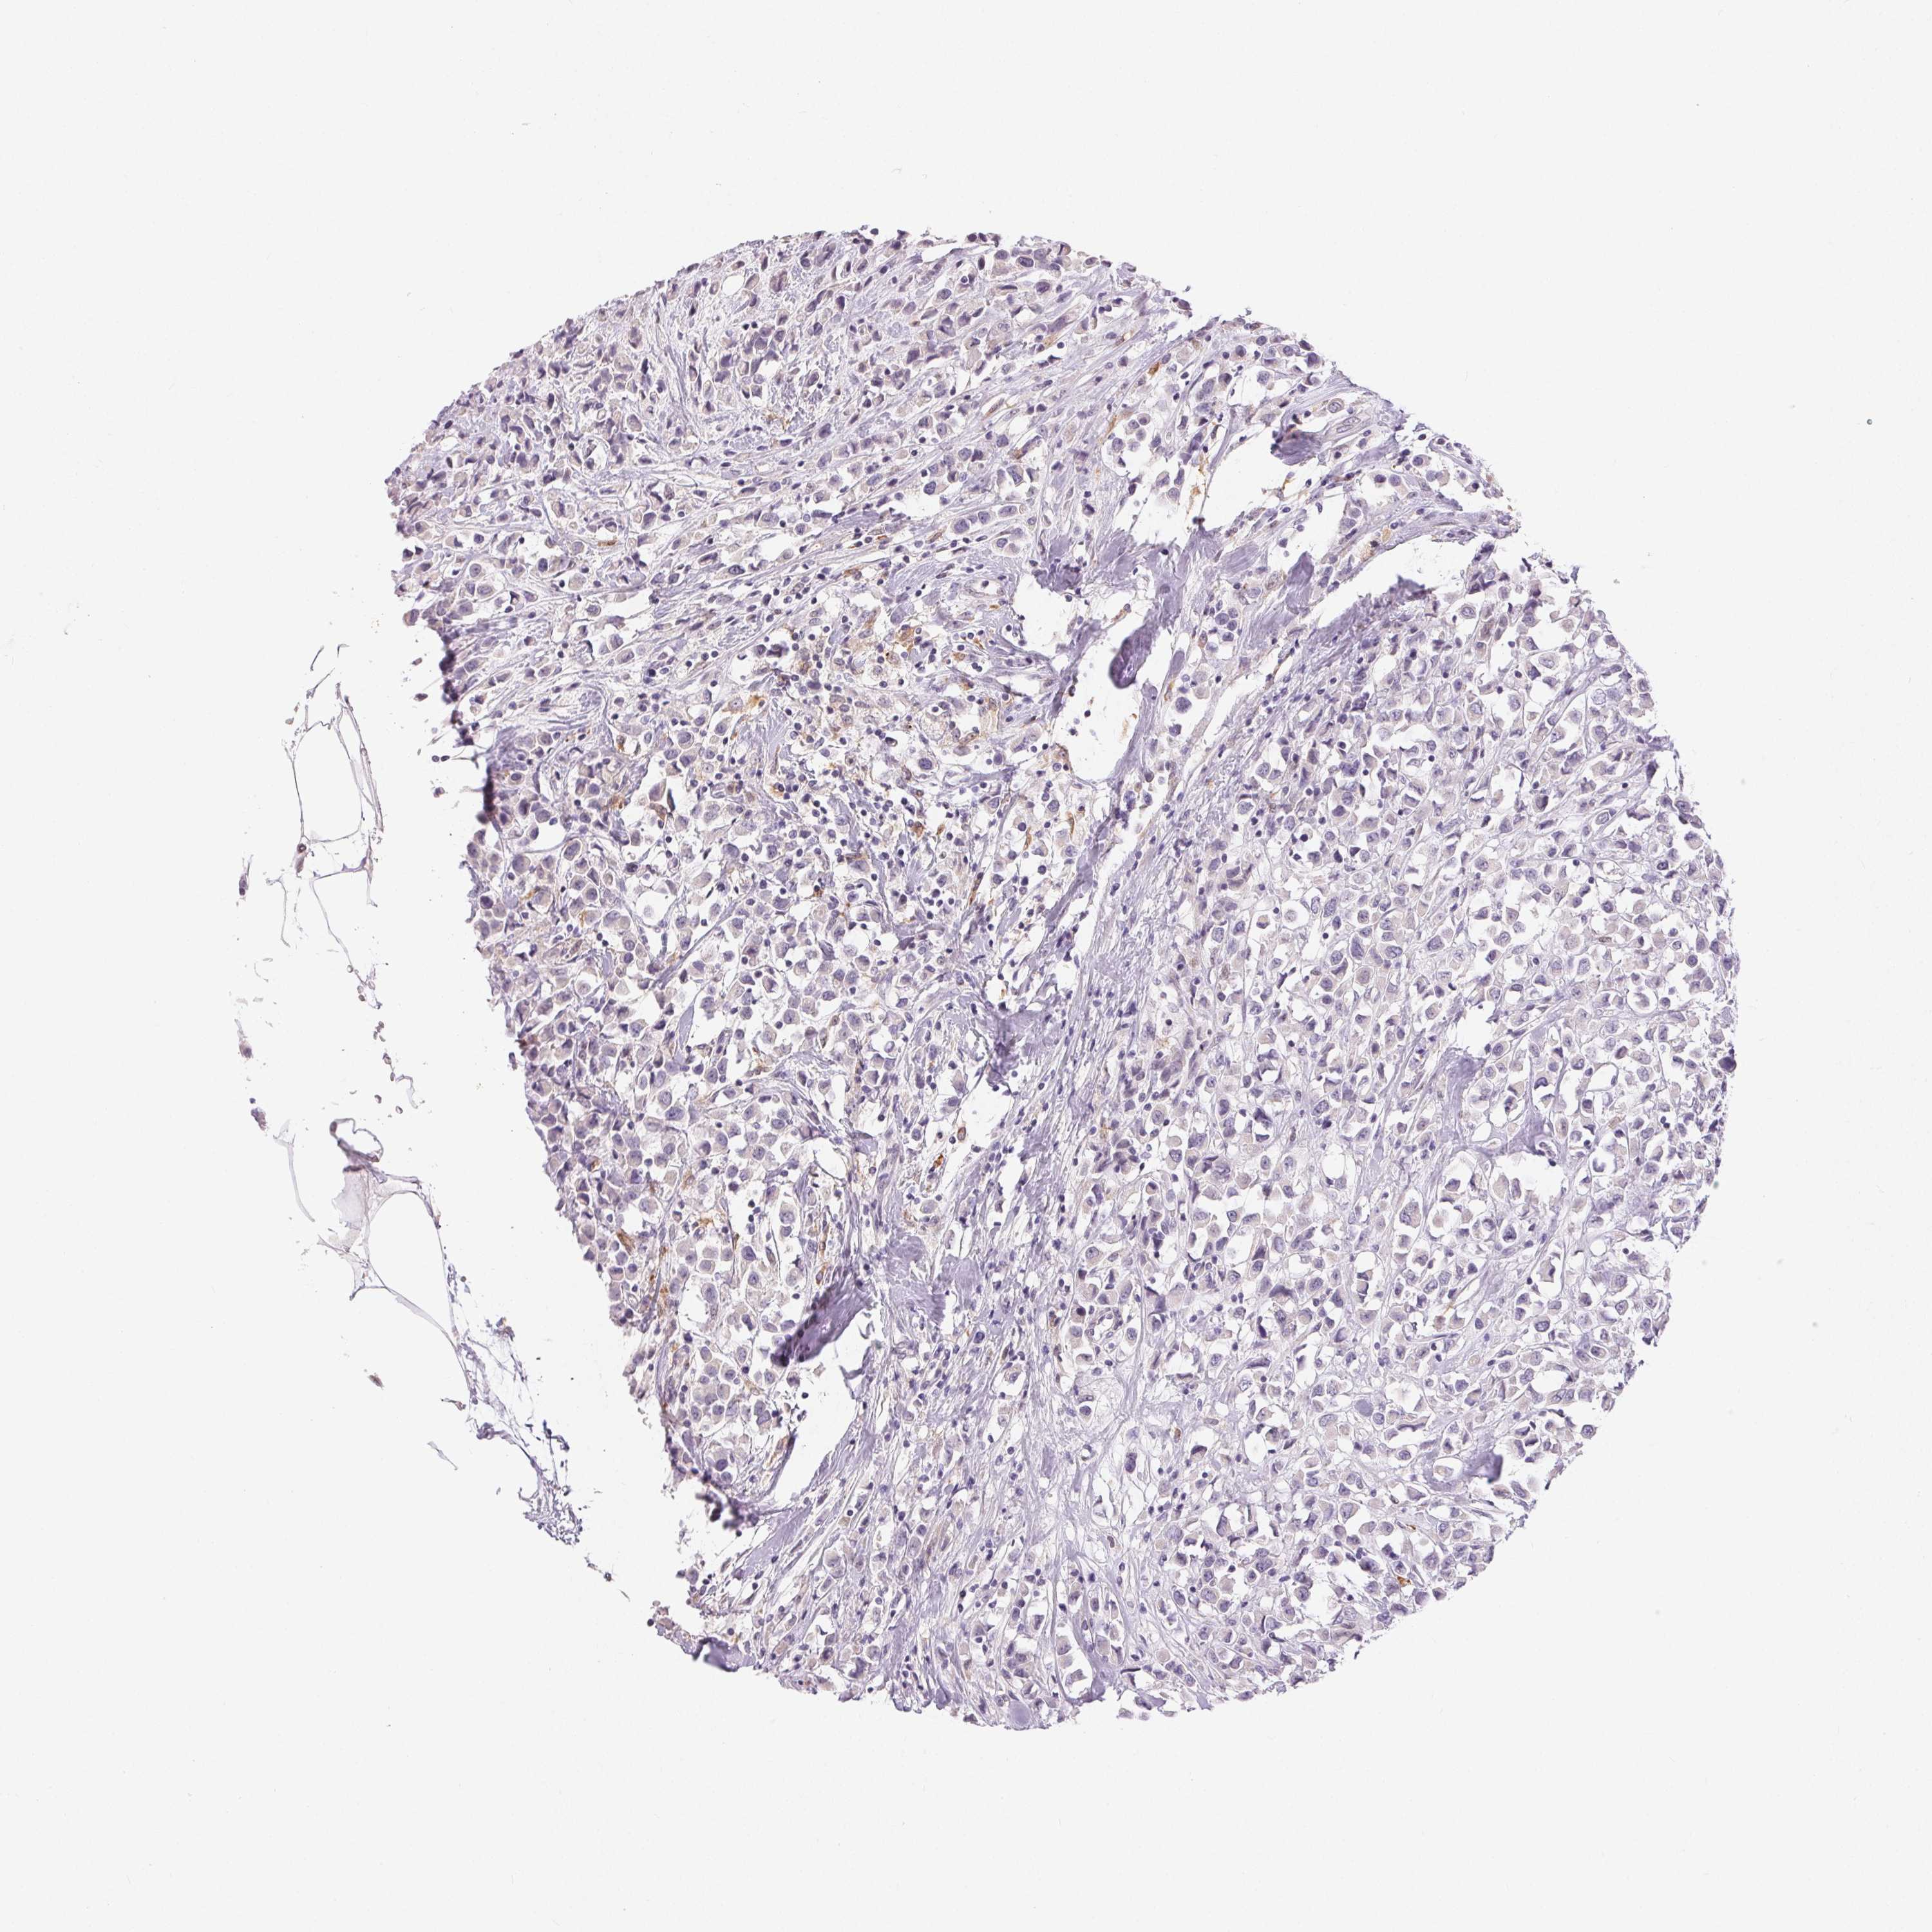

CANCER BREAST CANCER Show tissue menu

BRCA TCGA BRCA VALIDATION PROTEIN EXPRESSION

ANTIBODIES

AND

VALIDATION